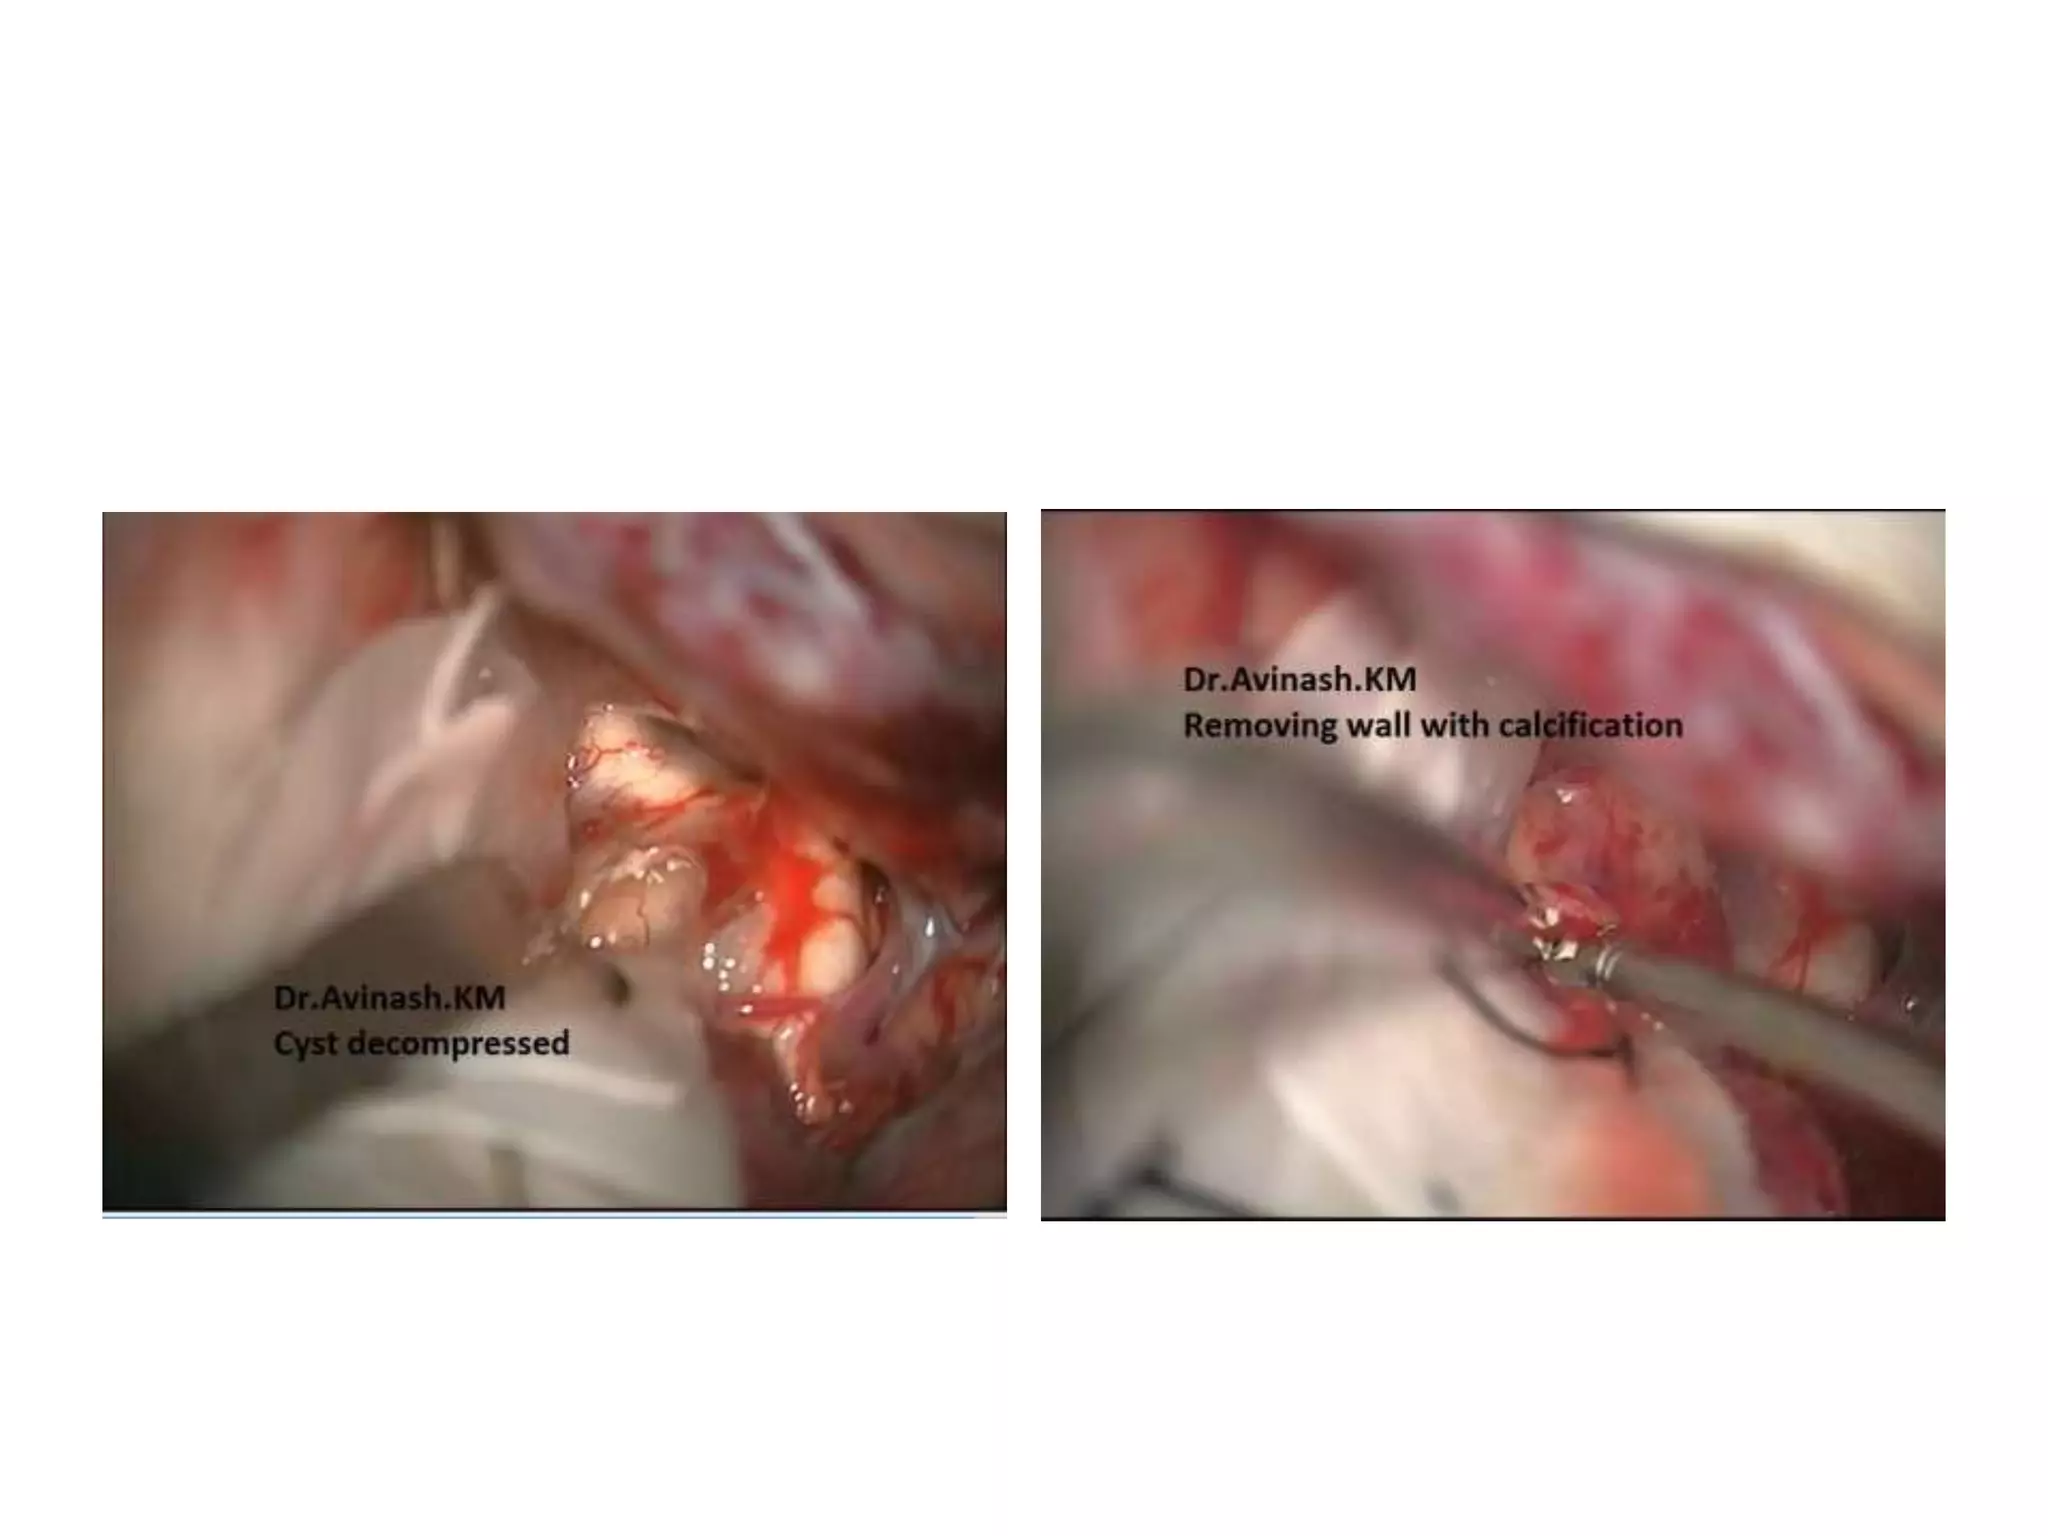

Craniopharyngioma

Cyst of craniopharyngioma

FIGURE 4. The capsule of the cystic craniopharyngioma was firmly attached to the left

hypothalamus, the stalk was dislocated to the right side (Patient 6). The outgrowth of the

craniopharyngioma from proximal stalk is recognizable A. Complete removal of the capsule was

possible, but produced subpial blood injection over the left hypothalamic surface B. MRI scan

revealed a small ischemic injury in the left hypothalamus C. This patient had transient sleep

disorder, moderate hyperphagia and memory problems (see also a supplemented video

material 1).

FIGURE 2. In this cystic craniopharyngioma (Patient 5), the stalk was centrally

infiltrated close to the pituitary and could not be preserved A. The incipient third

ventricle entrance is seen from intracavitary view. The slit into the third ventricle is

still covered with tumour capsule B. Complete removal of the capsule opened the

third ventricle C. Petehiae in the hypothalamus bilaterally resulted from apparently

gentle traction and blunt dissection of the capsule away from the hypothalamus

D. Psychoorganic change, disorientation and memory deficits were noticed in less

than a week after surgery, the transient sleep disorder become apparent in the

second week postoperatively (see also a supplemented video material 2).